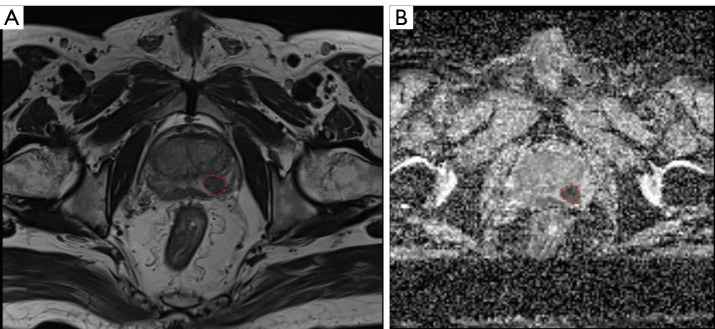

Results: Features were extracted from T2-weighted imaging (T2WI) sequences and apparent diffusion coefficient (ADC) maps based on bpMRI radiomics. From 3662 radiomics features, 10 stable radiomics features were selected for model construction based on intraclass correlation coefficients (ICCs). Three diagnostic models for csPCa were constructed. The area under the curve (AUC) values for the PI-RADS-scoring model, which was based on visual assessments by radiologists, were 0.8271, 0.7905, and 0.8331 in the training, test, and external validation sets, respectively; while those for the clinical scoring model were 0.9236, 0.8846, and 0.8378, respectively; and those for the radiomics model were 0.9790, 0.9584, and 0.9523, respectively. There were significant differences between the radiomics model and the PI-RADS-scoring model (P<0.001) in both the training and test sets. The P value for the radiomics model and clinical scoring model in the training set was <0.001, while that in the validation set was 0.056. Overall, the AUC values for the three models indicated that the diagnostic performance of the bpMRI radiomics model, which was based on T2WI sequences and ADC images, for csPCa was better than that of both the PI-RADS-scoring and clinical scoring models.

Abstract Image